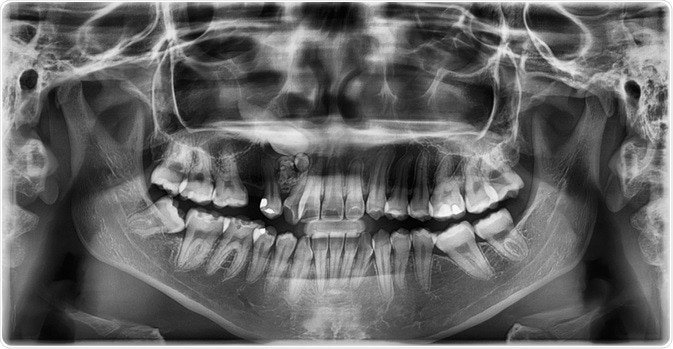

Gardner syndrome is often first identified in a dental clinic, as it is associated with odontomas and impacted teeth at multiple sites that can be both permanent and supernumerary. In fact, about 30% of patients with Gardner’s syndrome have one or more dental anomaly.

Image Credit: Rames Khusakul / Shutterstock.com

Maxillofacial involvement is very common in these patients and can involve skin cysts, pigmentation, and various radiographic anomalies. Odontomas also arise in the paranasal sinuses and mandible, and are rarely painful, generally occurring after puberty.

Both osteomas and odontomas may cause the face to become asymmetric. Both sharply-defined radio-opaque lesions as well as fuzzy radio-opaque lesions can be visualized in patients with Gardner's syndrome.